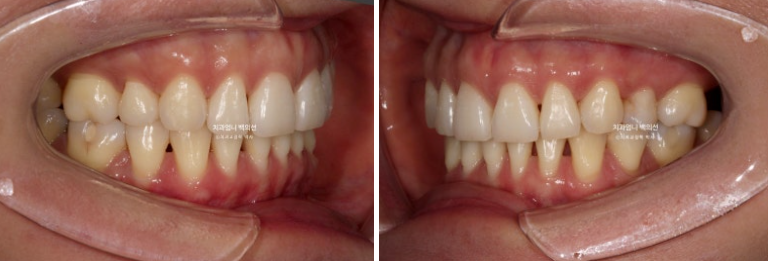

23.08~25.06

옥니였던 위 앞니 각도의 개선이 뚜렷하며 뒤로 밀려있던 아래턱이 다시 나오면서 안모가 좋아졌습니다.

옆모습에서 아래턱의 위치 변화가 좀 더 뚜렷하게 확인됩니다.

옥니였던 앞니가 역교정을 통해 정상으로 개선되어 다물었을 때 뒤로 밀렸던 아래턱이 이제 편하게 물립니다.

아래턱이 뒤로 밀리는 바람에 무턱처럼 보였던 부분도 개선이 되었습니다.